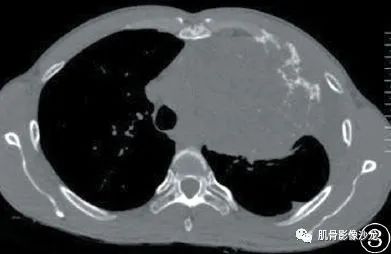

女,36岁,左上胸疼痛8月。

胸部CT示左侧胸腔见混杂密度肿块影,其内可见多发点片状钙化影及条片状更低密度影,增强后肿瘤可见轻度不均匀强化,左侧第2前肋见溶骨性骨质破坏。

术中所见: 左侧胸腔纵隔可见一巨大不规则肿瘤,直径约20cm × 15cm × 12cm,肿瘤蒂部较宽,与左侧第2 肋骨融合,分界不清,其中第2 肋骨骨质破坏,与纵隔胸腺、无名静脉紧密粘连,与左上肺、胸壁粘连,左侧胸腔可见少量血性积液。

病理诊断:去分化软骨肉瘤